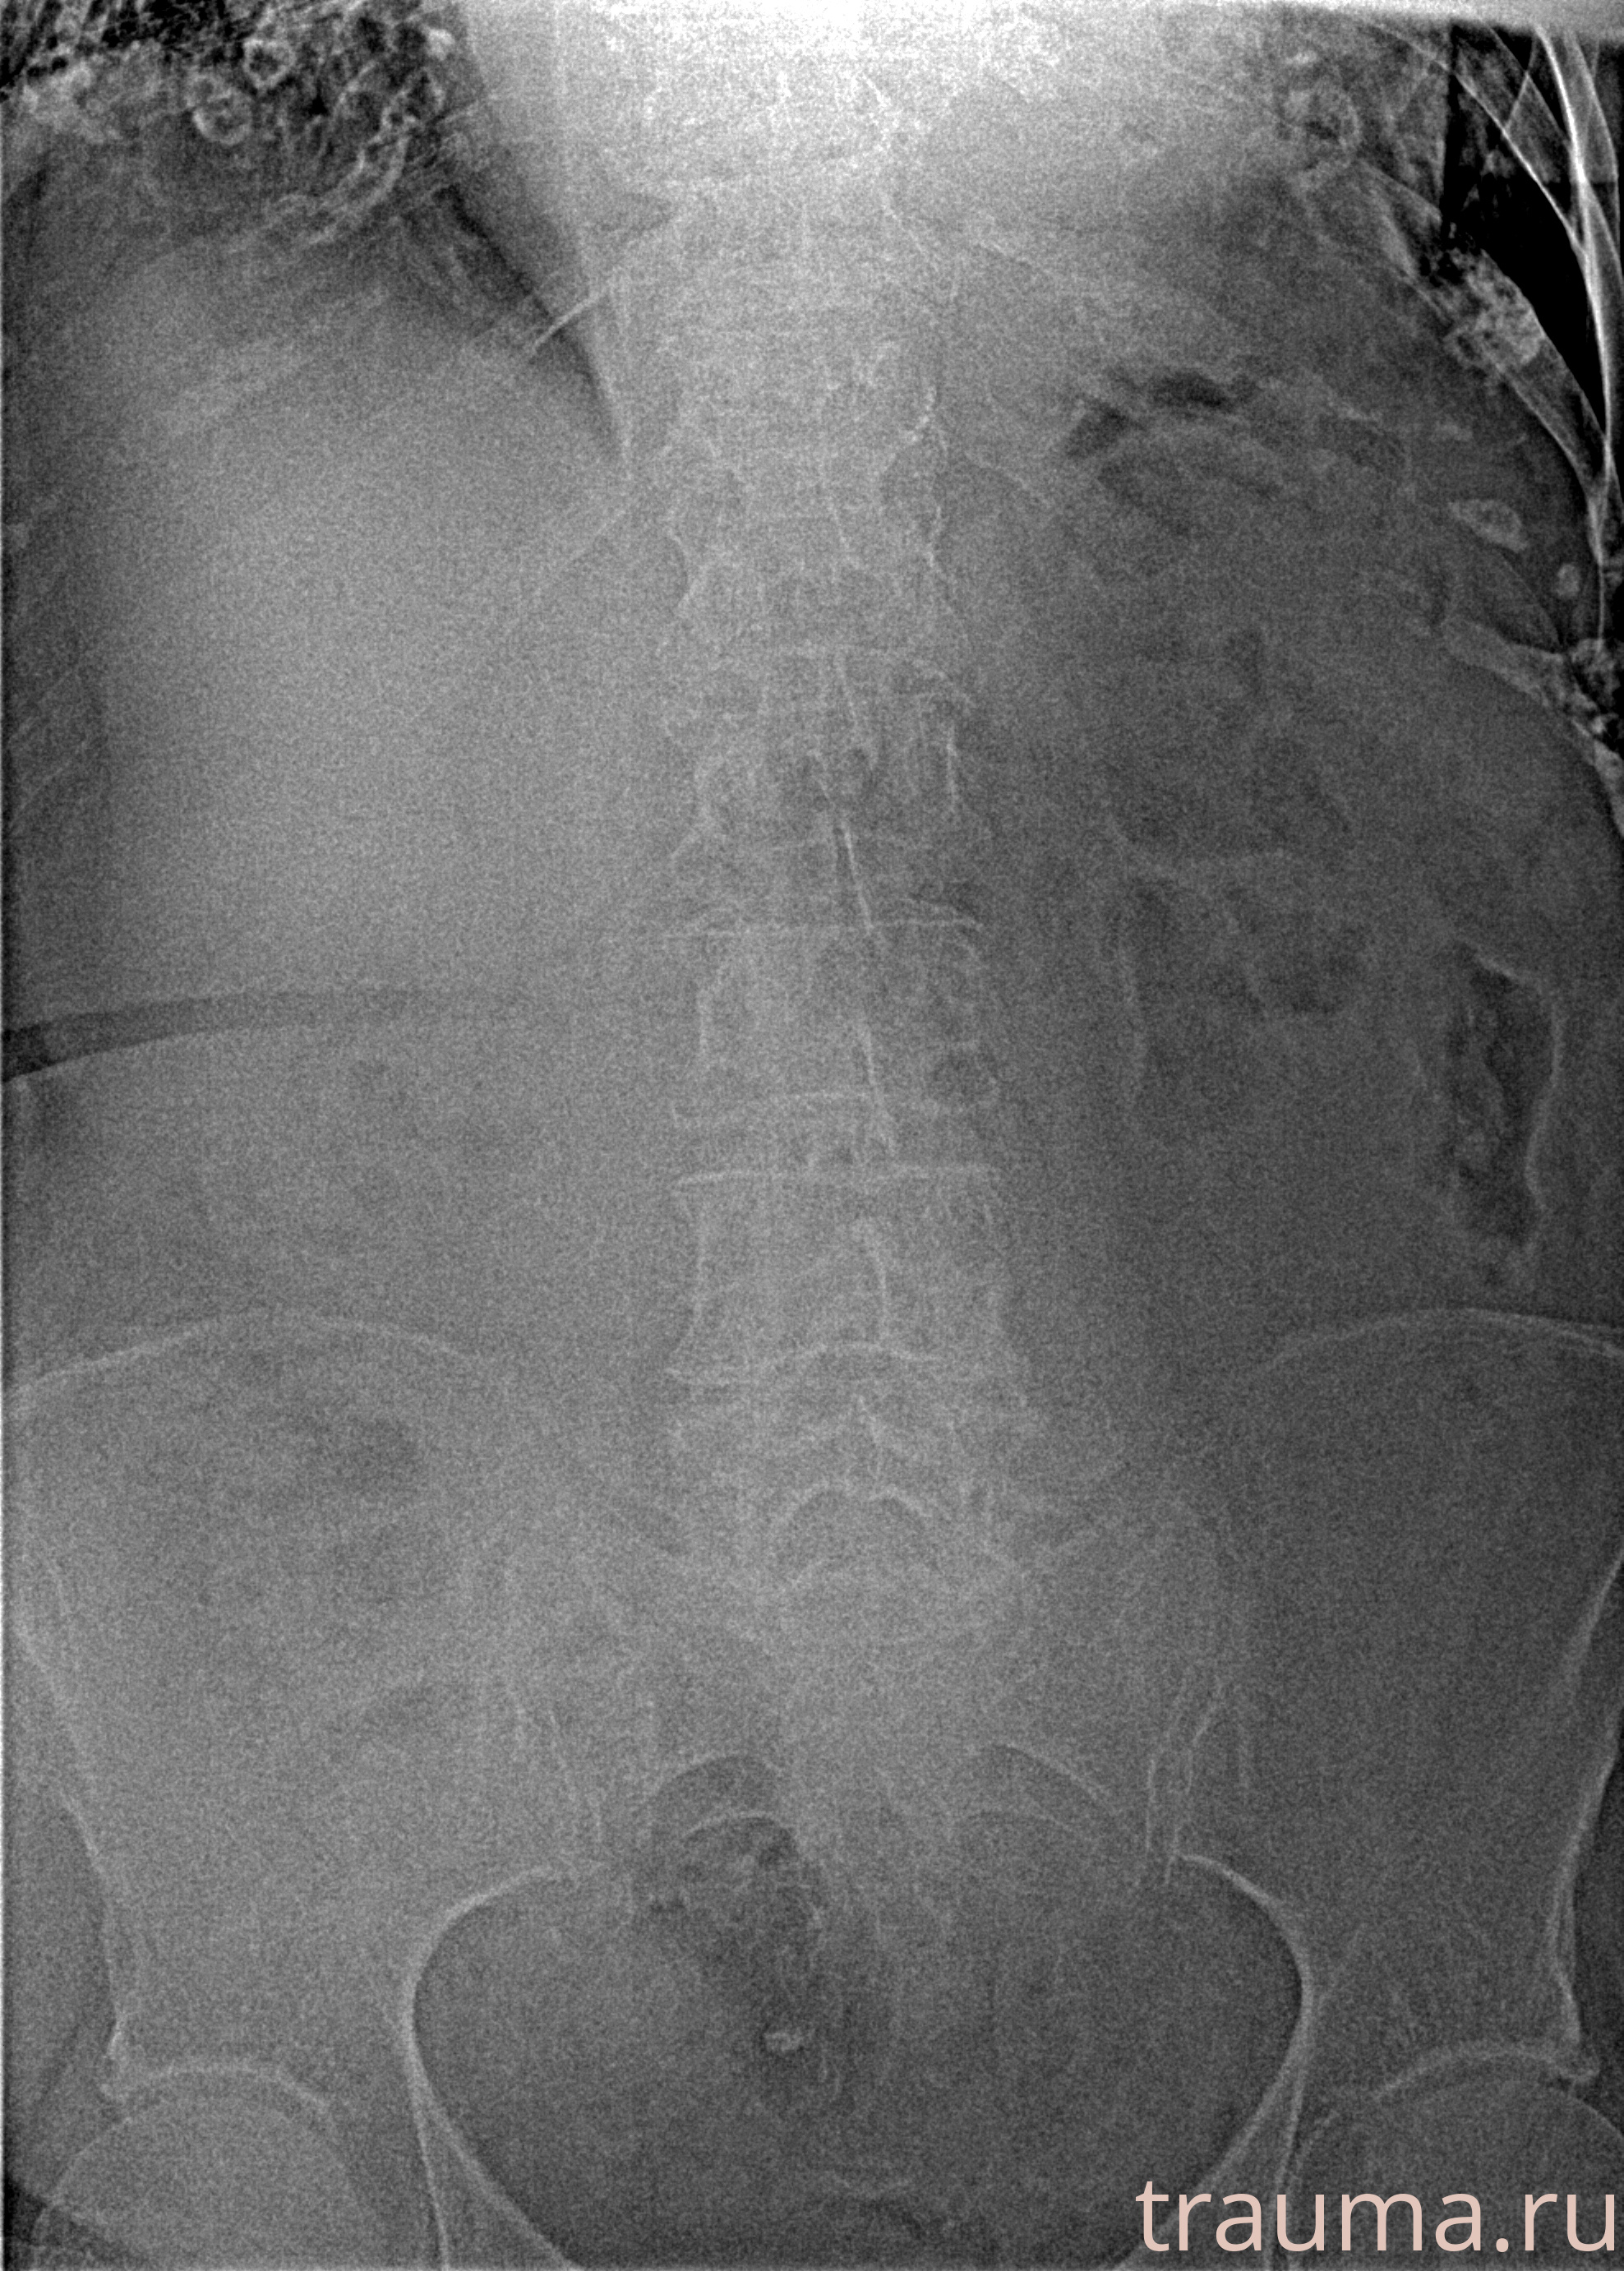

Рентгенограммы

Рентген на дому: по вашему адресу приезжает врач-рентгенолог, травматолог-ортопед с мобильным рентгеновским аппаратом, проводит диагностику травмы или заболевания, делает необходимые рентгенограммы, дает рекомендации по дальнейшему лечению. Получить качественные снимки в домашних условиях возможно благодаря уникальной методике, разработанной МосРентген Центром для института  Склифосовского